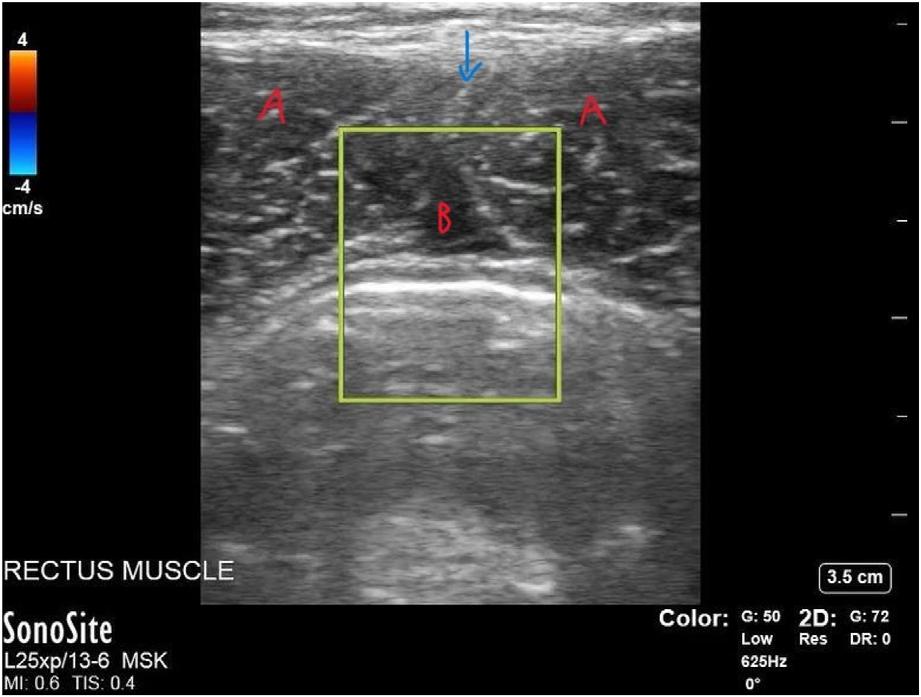

Kneejointswerescannedusingahigh-frequencylinear probeinthesagittalplane,startingattheanteriorkneeinthe suprapatellarregion(Image1A).Initialorientationofthe probecollectedviewsofthefollowingstructuresinrelationto theprobemarker:patella(inferioraspectoftheview);joint

capsule;anddistalfemur(superioraspectoftheview),as seenin Image1B (normalview).Imagescapturedinclude variousviewsinthedescribedorientationalonga

Image1. (A)Theorientationoftheprobeplacedinthesagittalplaneinthesuprapatellarregionwiththeprobemarkerorientedcranially; (B)ascanshowinganormalkneewiththetriangleindicatingthedistalfemurandthesquaremarkingthepatella.